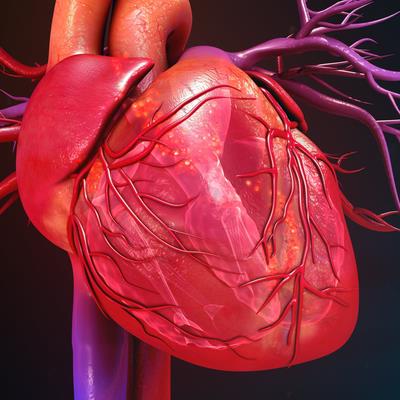

Inflammatory Cardiomyopathy: From Pathogenesis To Precision Therapy